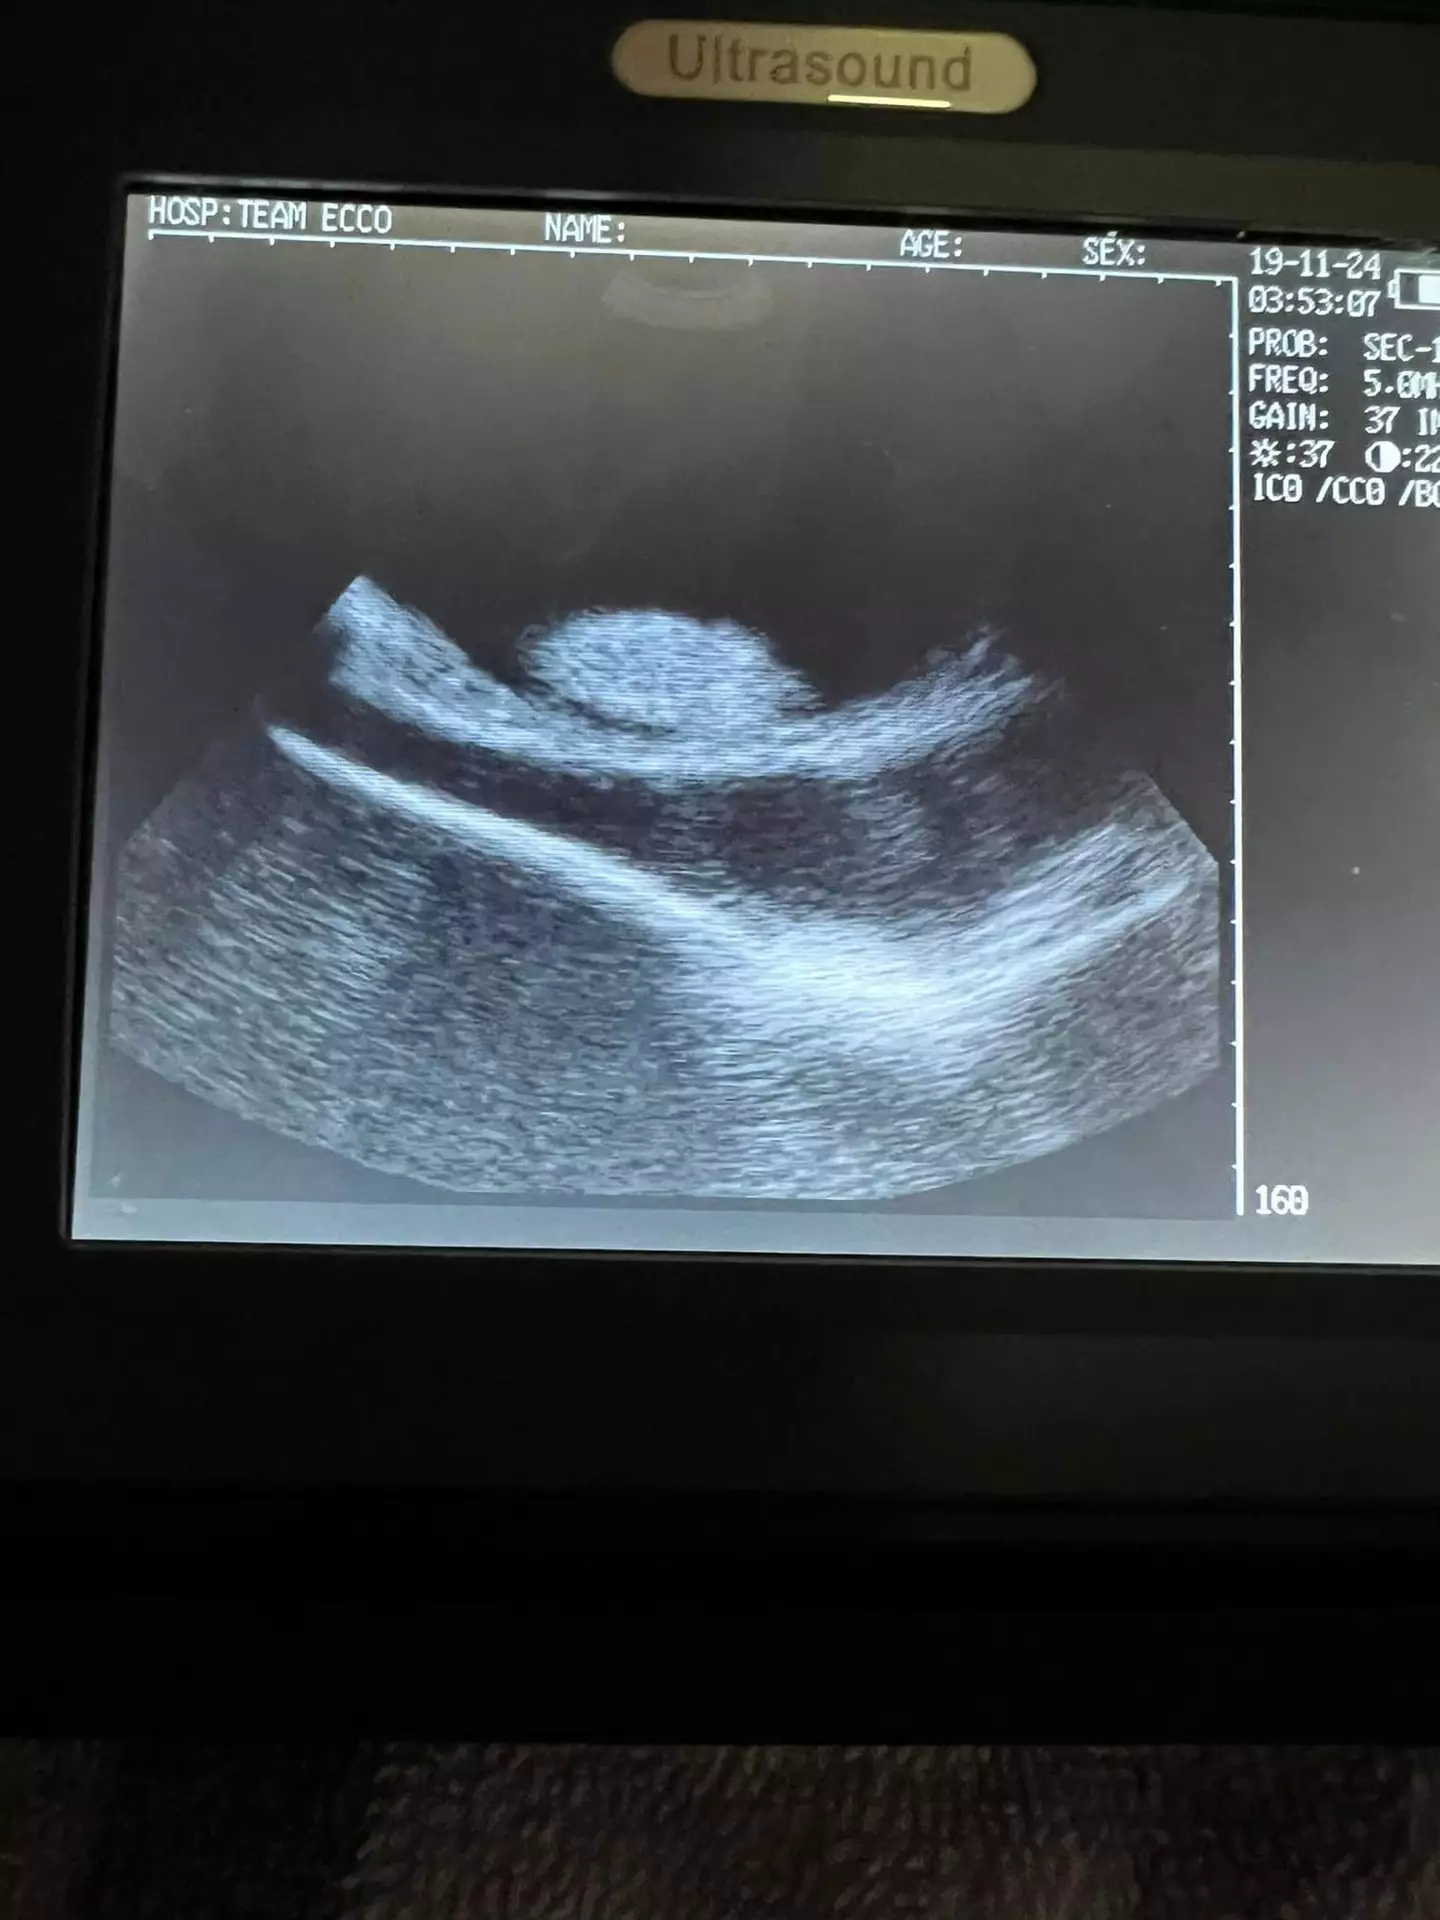

Staff at Aquarium and Shark Lab by Team Ecco in Hendersonville thought that Charlotte's swollen tummy could have been cancer when they noticed it back in September, but examinations have revealed that the creature is in fact pregnant.

Ramer believes that the expectant mom could be carrying up to four stingray pups and is due to deliver the babies at any time, since the typical gestation period for a stingray is three to four months.